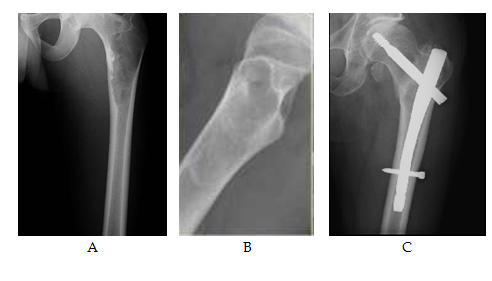

Excluded from this study any patient who already developed pathological fracture. Different types of fixation either surface plating (dynamic hip screws) (Figure 3 & 4) medullary (Gamma nails) (Figure 5) or external fixation in cases unsuitable for surgery (Figure 6) were used according to the type and the site of the deformity. In tibial cases, we used the tourniquet without blood evacuation in the limb.

Figure 5 (A and B) show an osteolytic lesion of the proximal end femur with high risk factors by increasing pain, the size of the lesion, radiographic appearance, localization, transverse/axial/circumferential involvement of the cortex and the scoring system of Mirels.

(C) Shows post operative fixation after one year with mild resolution of the cyst and heterotrophic calcification at site of nail insertion and head of femur.